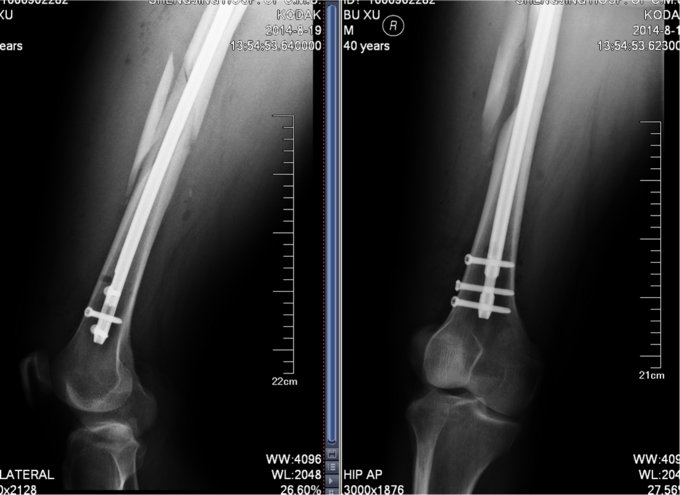

诊断:右股骨干骨折 患者入院后急诊行右胫骨结节骨骼牵引术,术后维持患者长度,减轻患者疼痛,完善相关检查后,行右股骨干骨折闭合复位髓内针内固定术。